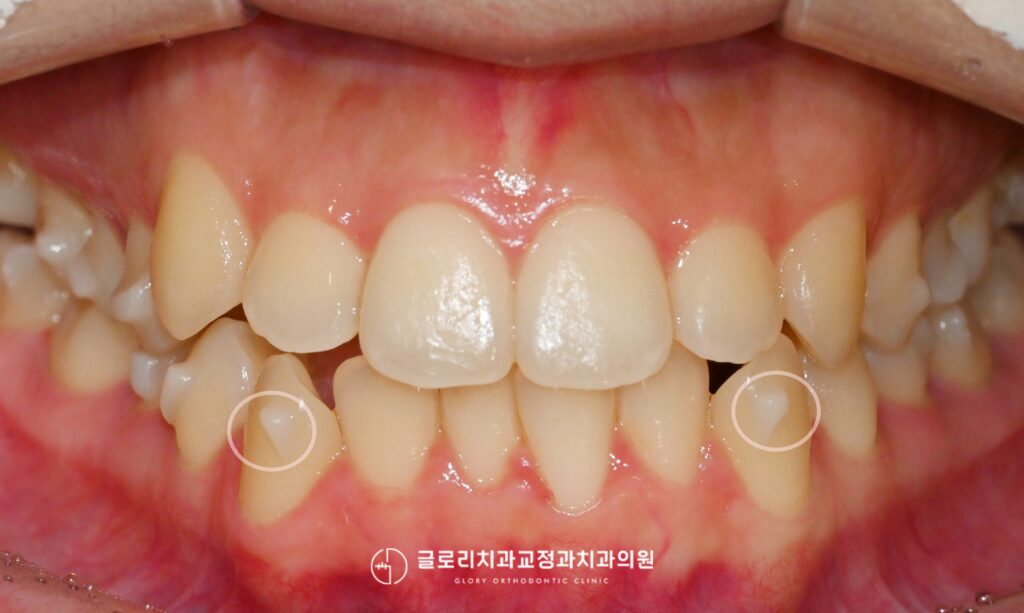

중랑구 교정치과 앞니가 삐뚤고 입이 나와보인다면? 발치교정을 통한 골격성 2급부정교합 개선 가능합니다.

안녕하세요, 교정과 전문의 김정은입니다. 앞니는 단순히 음식을 자르는 기능을 넘어 첫인상을 결정짓는 중요한 심미요소를 담당하는 부위입니다. 특히나 웃을때 제일 먼저…